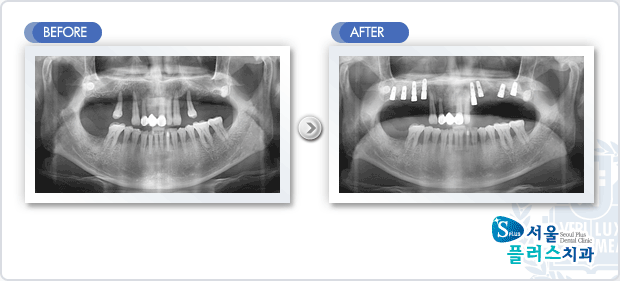

[임플란트] 임플란트 - 상악 좌우 구치부 상실부위 임플란트 식립